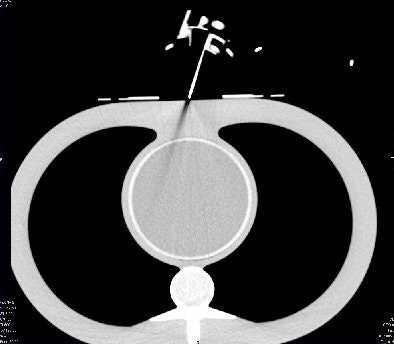

![]() |

| CT image shows that Robopsy does not distort the image and creates no shadows that may obstruct the view of the needle's position. |